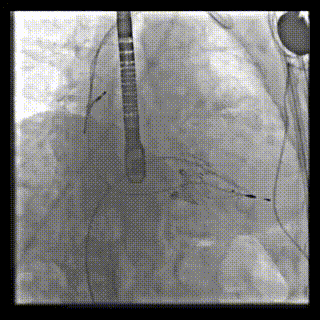

2021年12月24日,復(fù)旦大學(xué)附屬中山醫(yī)院葛均波院士團(tuán)隊(duì)成功應(yīng)用LuX-Valve Plus為一例極重度三尖瓣反流(TR)合并房顫、房缺的患者完成了經(jīng)血管三尖瓣置換術(shù),這是在前基礎(chǔ)上,本周完成的第三例經(jīng)血管三尖瓣置換手術(shù),葛均波院士、周達(dá)新教授等與心外科魏來教授、賴顥教授,心超室的潘翠珍教授、李偉教授及麻醉科的郭克芳教授共同完成了本周手術(shù),均獲得圓滿成功!患者術(shù)后超聲顯示無TR,臨床癥狀明顯改善。本周手術(shù)的成功也為LuX-Valve Plus救治性臨床研究添上了濃墨重彩的一筆。

本周三例接受LuX-Valve Plus經(jīng)血管三尖瓣置換術(shù)的患者中,第一例患者為冠狀動(dòng)脈旁路移植術(shù)+Bentall+二尖瓣成形術(shù)后;第二例患者為永久起搏器植入術(shù)后,存在跨三尖瓣導(dǎo)線;第三例患者合并房顫、房缺及左心耳封堵術(shù)后。

三例患者入院后,葛均波院士團(tuán)隊(duì)周達(dá)新教授、潘文志教授、張?jiān)床┦俊㈥惿┦考靶某业呐舜湔浣淌?、李偉教?/strong>對(duì)患者的情況進(jìn)行詳細(xì)評(píng)估和討論,最終決定為三例患者選擇LuX-Valve Plus40mm、50mm和50mm型號(hào)的瓣膜進(jìn)行手術(shù)治療。手術(shù)后即刻拔除氣管插管,術(shù)后患者三尖瓣反流癥狀得到顯著改善,復(fù)查心超結(jié)果顯示人工三尖瓣瓣膜支架固定穩(wěn)定,瓣葉關(guān)閉形態(tài)未見異常,未見明顯反流。

LuX-Valve Plus是LuX-Valve系列產(chǎn)品的第二代,采用的是經(jīng)血管入路的全新輸送系統(tǒng),其設(shè)計(jì)開發(fā)過程得到了上海中山醫(yī)院葛均波院士及其團(tuán)隊(duì)的精心指導(dǎo),研究結(jié)果提示瓣膜植入的安全性和有效性俱佳,尤其瓣膜獨(dú)特的設(shè)計(jì)使其具有極佳自適應(yīng)性,本周三例患者病因及解剖結(jié)構(gòu)各具特點(diǎn),但均可從LuX-Valve Plus植入術(shù)明顯獲益。目前,LuX-Valve Plus已在全國各中心開展救治性臨床研究,相信未來定會(huì)為更多的三尖瓣反流患者帶來福音。